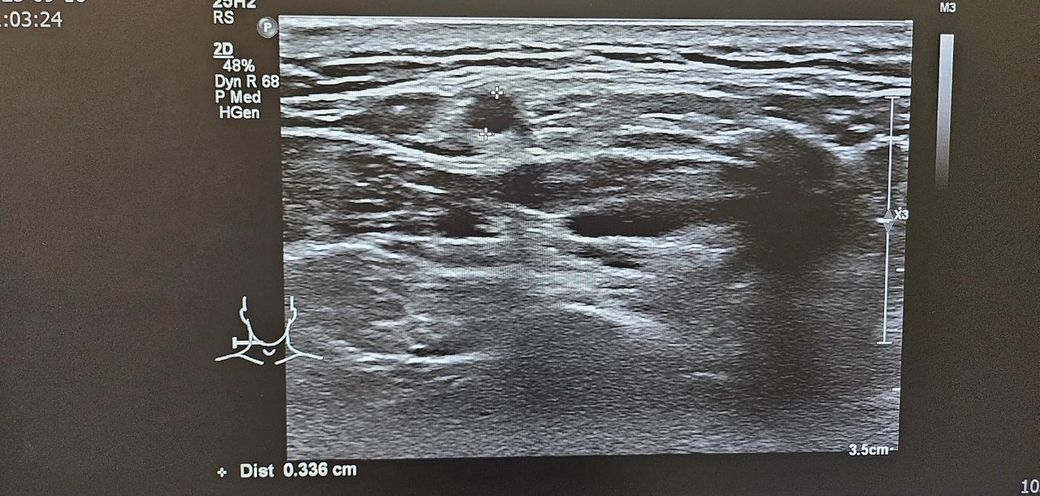

경부 초음파찍었는데 초음파 사진좀 봐주세요.. .

목통증이 있어서 초음파를 했는데

여러개가 부어있다고 하셨습니다

• 3번 째 사진

초음파 소견으로는 림프절들이 보이며 부어 있다 정도로 보입니다. 이외에 특별하나 소견이 따로 있거나 해 보이지 않습니다. 약물 치료를 하여도 회복이 되지 않다면 추가적으로 약물 복용을 해주며 경과를 지켜보거나 보다 정밀 검사를 통해서 다른 문제는 없는지 감별해보는 방향이 있겠습니다. 이비인후과적으로 재차 상담을 받아보시는 것을 권고드립니다.